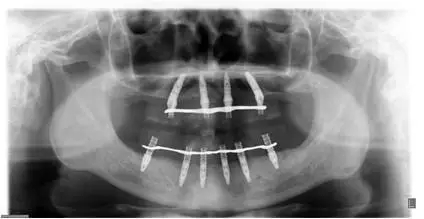

患者男性,51歲,全口無牙,下頜骨量尚可,上頜后牙區(qū)上頜竇底剩余骨高度嚴(yán)重不足,前牙區(qū)牙槽突較豐滿,主訴希望全口種植固定義齒修復(fù)。于2015年 9月接受種植治療:上頜采用All-on-4種植方案、下頜采用常規(guī)種植6顆種植體方案,種植后行即刻修復(fù)(圖1-2)。